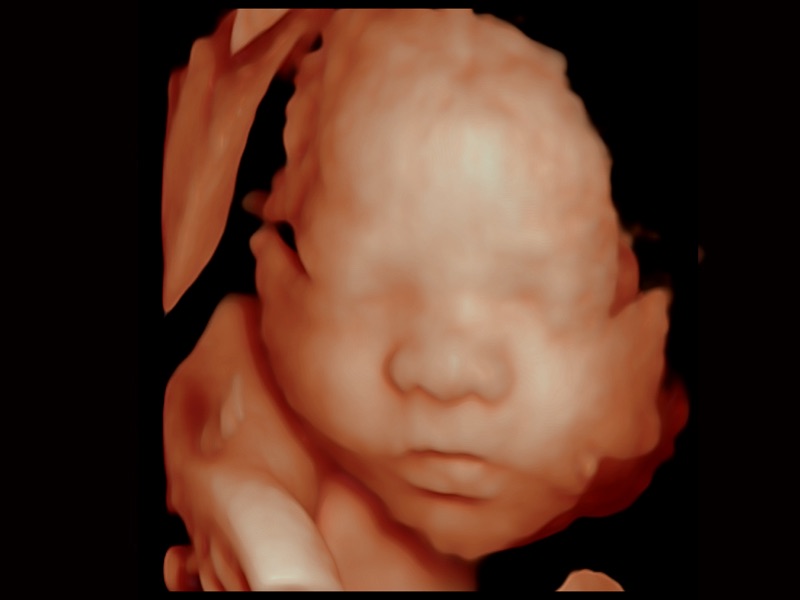

三維光影成像技術(shù)采用新型的渲染方式,增強(qiáng)邊緣信息,使得輪顯示清晰完整,為臨床提供豐富、直觀的三維結(jié)構(gòu),提供臨床診斷準(zhǔn)確性。

婦產(chǎn)科應(yīng)用